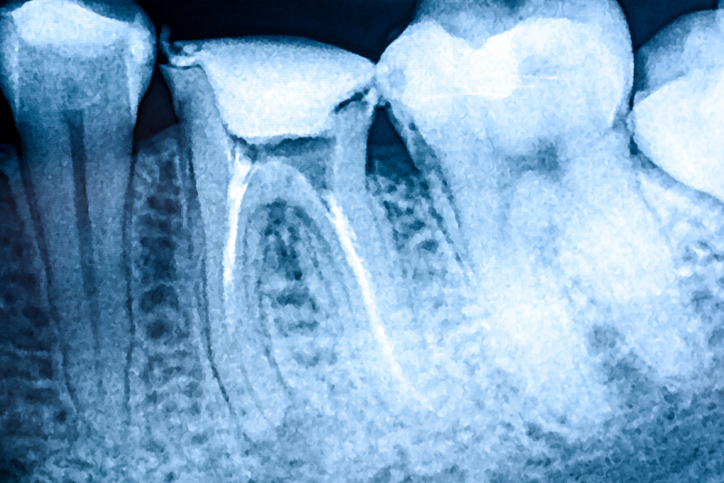

2. 페리어피컬 엑스레이

①특정 치아의 뿌리까지 자세히 촬영

②용도

●충치의 깊이 확인

●뿌리 염증(치근단 농양 등)

●신경치료(근관치료) 필요 여부 확인